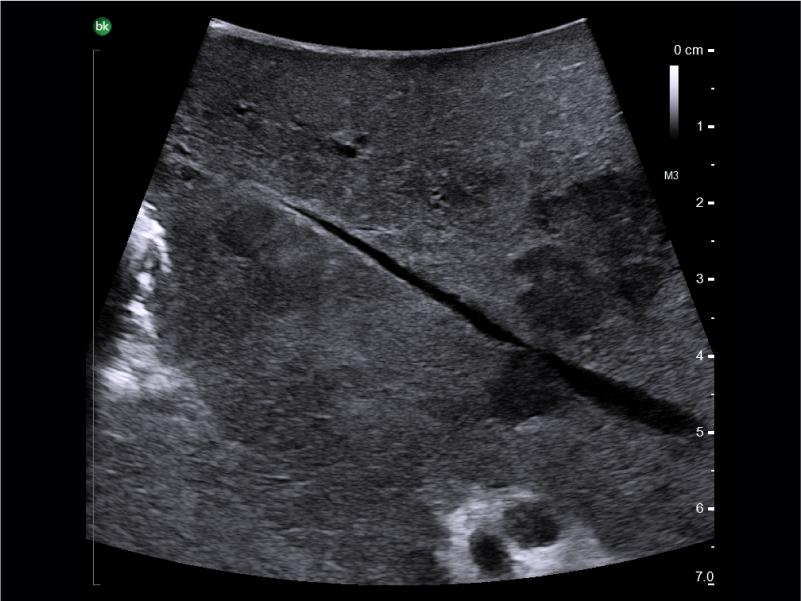

Liver mass, visualized with I-Shaped Transducer

Visualize hepatic and pancreatic tumors and guide needle placements

Active imaging supports liver and pancreas ablation procedures by helping you visualize lesions and blood vessels, identify healthy tissue vs. tumor, and guide and view needle placements.